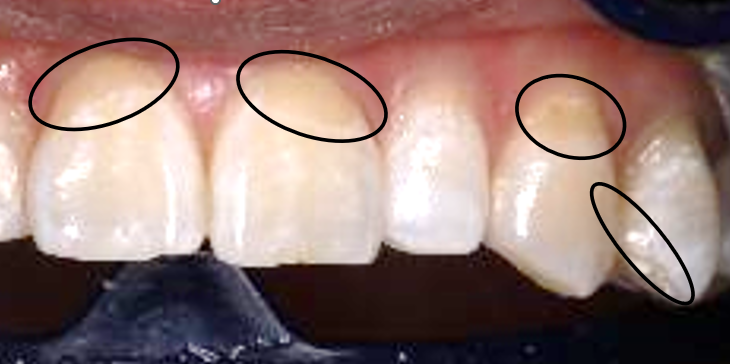

ちょっとわかりずらいのですが、ホワイトニング後に、元の色(A3)の歯のサンプルをあてた画像です。こちらの方が色の違いがよくわかる気がします😊

黒丸の部分が人工歯で、色が白くならなかった箇所です💦

また、お気づきかもしれませんが、私は体質的に元々歯に色ムラがあります(>_<)

この色ムラはホワイトニングをしても治りません⚠️

色ムラがあるまま白くなるのです!